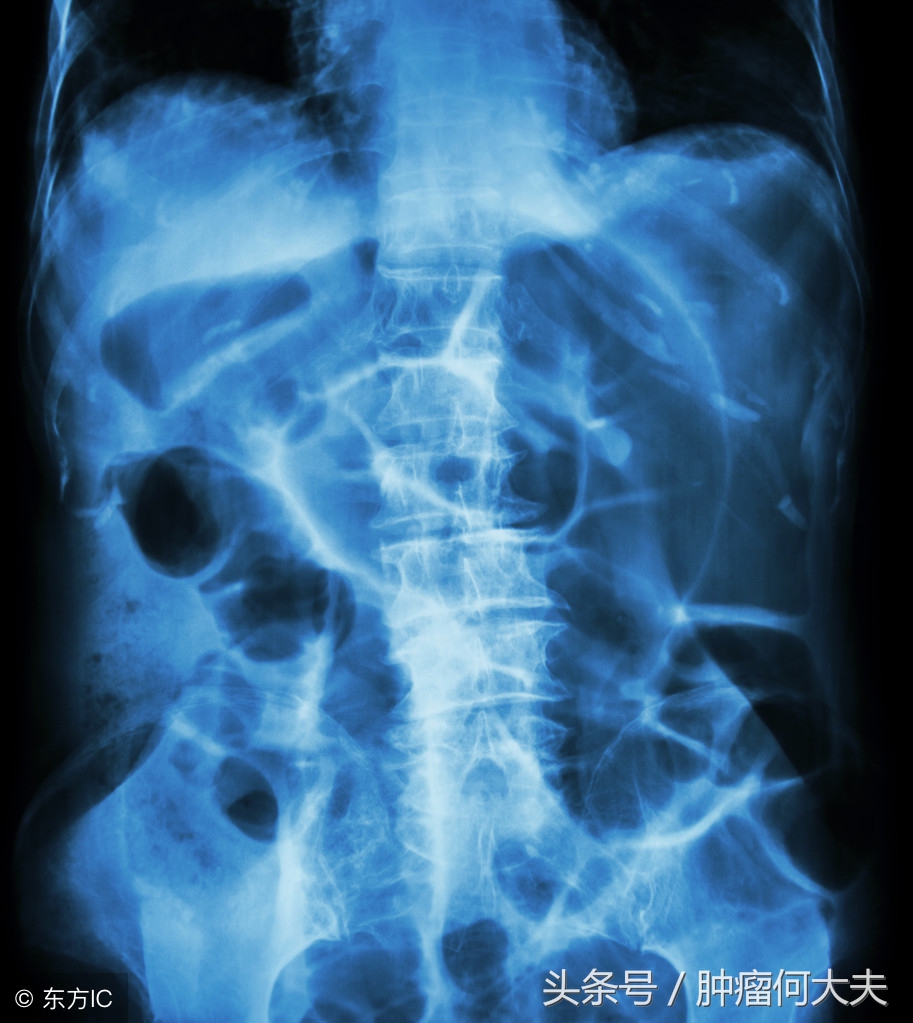

一周前王先生再次因腹胀伴发热,收住院,入院后化验检查提示①有感染,白血球偏高;②小肠梗阻,。造瘘袋每天有稀水样粪便排出,但量不多。在禁食,禁水,下胃管,负压引流同时,口服石蜡油,给予全肠外静脉营养支持,2天后患者腹胀未见明显缓解。后决定通过造瘘口处理,当时找了一根长约30厘米的尿管,后将尿管沿造瘘口插入,后用50ml注射器回抽,先抽出两管稀水样粪便,无明显臭味,抽第三管时候有阻力,后抽出小拇指大小的蔬菜叶团块(已经压缩在一起,但周围有菜叶样子,依然能看出它的原型),这个小蔬菜疙瘩被抽出后,哗哗的流出约有800ml稀便,而且粪水奇臭无比,此后患者腹胀明显好转,发热也逐渐好转。王先生回忆自己吃过炒空心菜。

肠梗阻

肠癌病人,其中有不少都被迫造瘘,造瘘术后,大便改道不仅给患者带来生活上的麻烦,需要定期进行造瘘口袋清洁置换,而且有的患者由于造瘘口位置高,尤其是回肠造瘘,饮食不注意就会出现肠梗阻,弄不好也可能会致命。回肠造口是回肠末端在腹壁的开口。人体消化道的每一部分都发挥着重要的作用。食物在人的胃内形成食糜,在小肠内通过进一步消化,小肠能够吸收食物中绝大部分的营养,而结肠负责吸收水分,使便成形。回肠造口术后,消化的食物不再经过大肠,容易再经过腹壁的肠道时被截留,一旦发生这种情况,大概率就会阻塞。食物阻塞的结果就是,可能引起腹部痉挛,腹痛,腹泻等,饮食需要注意的是避免难以消化的食物,包括干果,椰子,红肉,菌类,空心菜,芹菜,豆角等食物。除饮食因素外,肠造口病人也要注意情绪因素,临床发现不少造口病人伴有抑郁症,抑郁状态会下调人体免疫力,导致病情复发。而开朗外向积极向上的精神状态有助于病情康复。